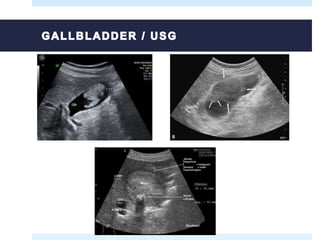

 Abdominal ultrasound (is the first to be performed after the patient any

symptoms or risk factors mentioned).

 Early-stage cancers, especially sessile polyps can not be seen.

 Typical image of gallbladder

cancer:

Focal or diffuse wall thickening

Intraluminal mass >2 cm arising from the

gallbladder wall

Hepatic mass that replaces or darkens the

bladder, commontly invades other organs

 Indicative findings suggesting that

the lesion is malignant:

Thickening of the wall (irregular and

aymmetrical) >1 cm

Nodular intraluminal mass or smooth, >1

cm, fixed to the wall of the bladder, which

does not move with the patient's

movements and has no acoustic shadow

CT and MRI may be useful in the diagnosis if ultrasound findings are indeterminate